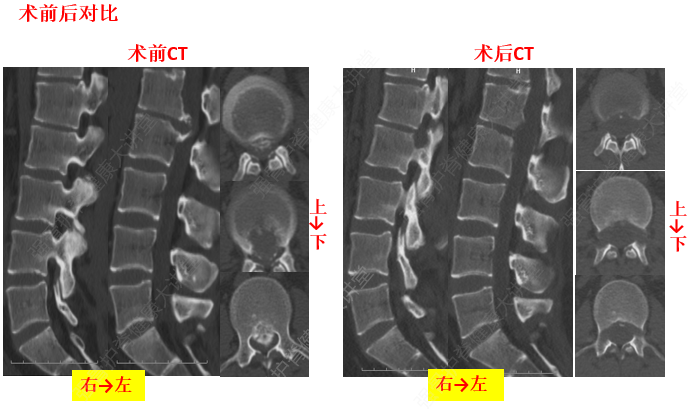

3、椎間盤與椎間韌帶的退變

椎間盤的退變是發(fā)生頸椎病的基礎(chǔ)既是產(chǎn)生本病的內(nèi)因,又是其較為普遍的病理改變。如頸部的長(zhǎng)期過(guò)度伸、屈活動(dòng)可使弓間韌帶(發(fā)生相應(yīng)的改變)變厚、彈力減弱,甚至發(fā)生鈣化或骨化,直接壓迫脊髓。長(zhǎng)期過(guò)伸,可損傷前縱韌帶,突然的猛力后伸活動(dòng),可造成前縱韌帶與椎體前緣附著處的撕裂。反之,可造成后縱韌帶損傷或與椎體后緣附著處的撕裂。由于椎間盤的退變,首先出現(xiàn)韌帶松弛,繼而發(fā)生肥厚、鈣化或骨化反應(yīng)。韌帶鈣化部位與椎間盤受損平面相一致。本病患者項(xiàng)韌帶的鈣化是普遍的,可在頸后觸及條索狀物。